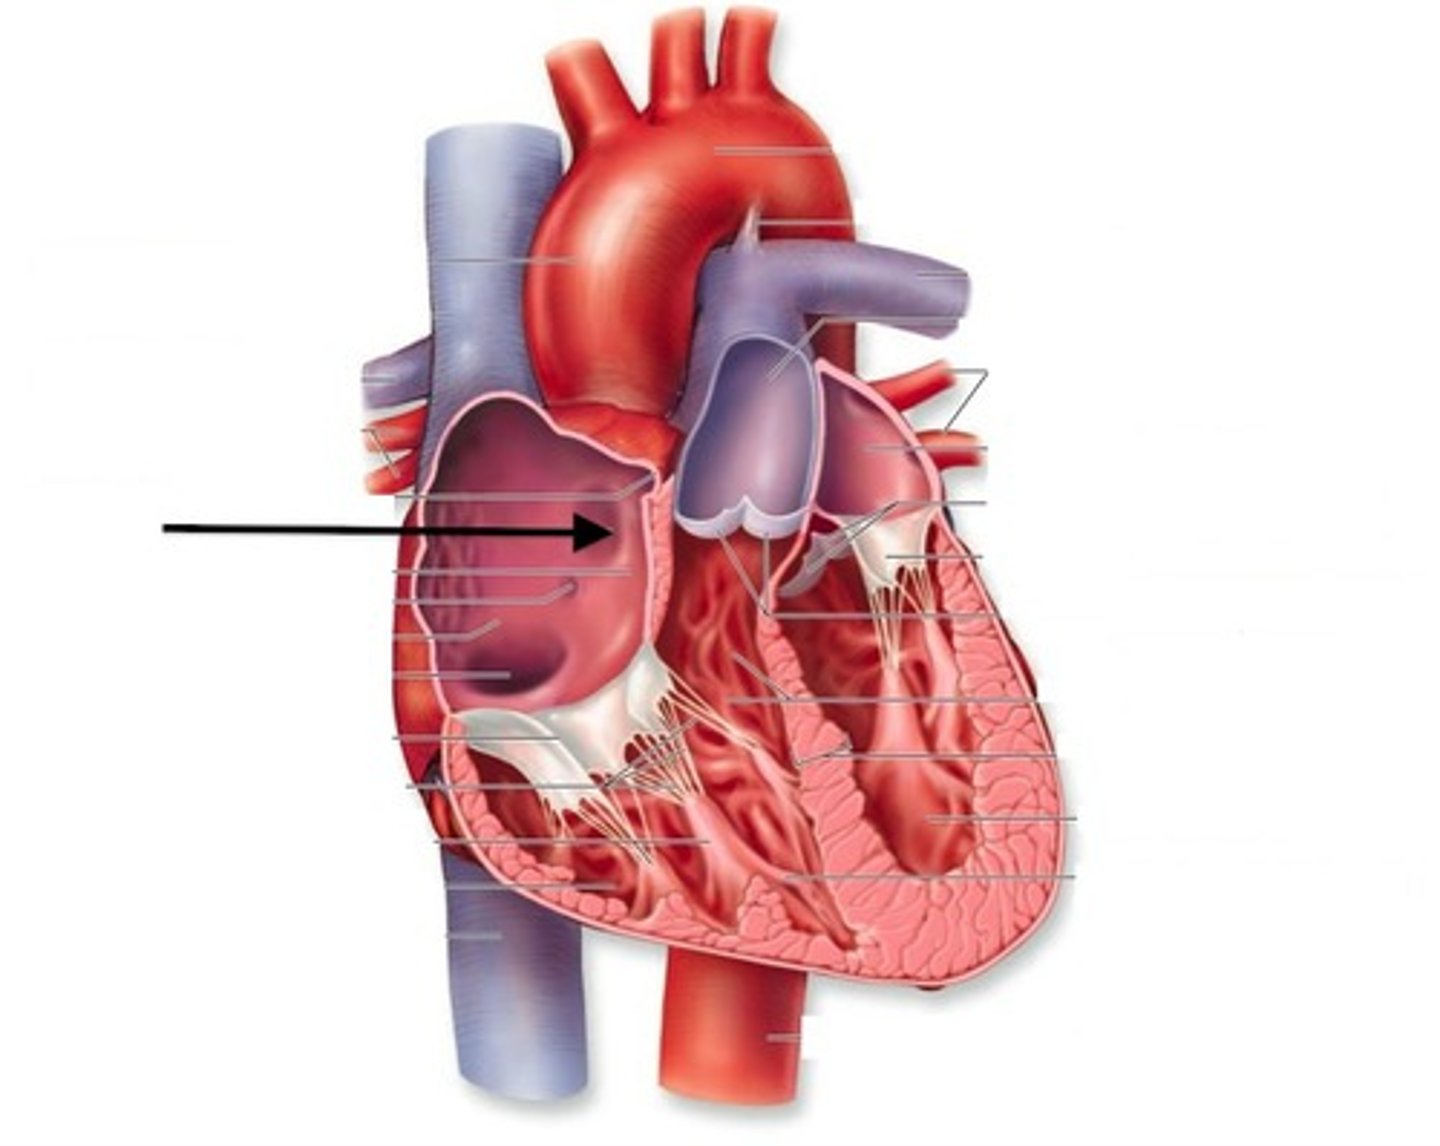

Superior Vena Cava

Inferior Vena Cava

Coronary sinus

The right atrium receives deoxygenated blood from:

The four pulmonary veins (right superior, right inferior, left superior, left inferior)

The left atrium receives oxygenated blood from:

From: Left atrium through the bicuspid valve

To: Aorta through semilunar valve to systemic system

The left ventricle receives blood from:

and sends it:

From: Right atrium through tricuspid valve

To: Pulmonary trunk (artery) through semilunar valve to lungs then pulmonary veins

The right ventricle receives blood from:

and sends it:

Atrioventricular valves (tricuspid and bicuspid)

Prevents back flow into atria

Semilunar valves (aortic and pulmonary)

Prevents back flow into ventricles